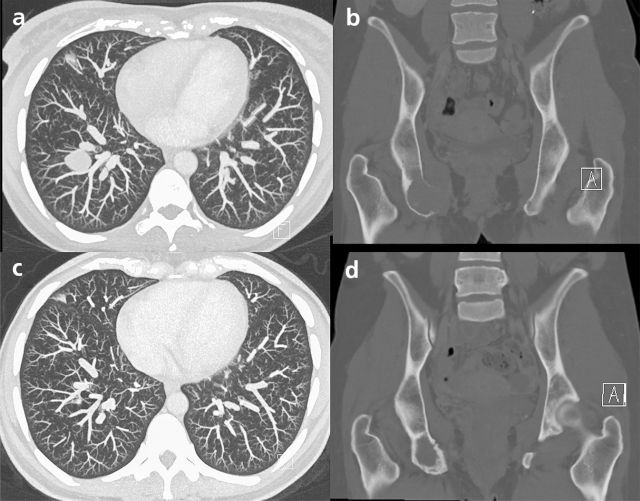

Was gibt es Neues in der Therapie des nicht-klarzelligen Nierenzellkarzinoms

Systemtherapien beim metastasierten nicht-klarzelligen Nierenzellkarzinom